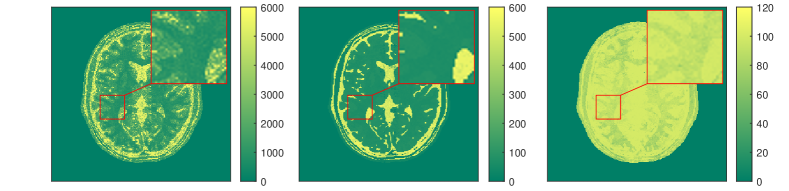

The results for each of the above mentioned algorithms can be found in Figures 3 and 4. We use the MRF reconstruction as initialization for the L-M algorithm, and compare that with the result of the BLIP algorithm when using a relatively refined dictionary. The advantage of integrated-physics approaches is evident by checking the reconstructions in Figure 3 as well as quantitatively by looking at the error maps in Figure 4. In this example, we have used a time series of the 1/8 Cartesian-subsampled k-space data (Fourier coefficients of magnetizations) of length 40. In the original MRF algorithm (typically requiring a large time series of k-space data), this test setting is far from yielding a reasonable result, while BLIP has improved a little by enforcing the projection to the Bloch manifold. But still one observes deficiencies. The method with integrated physics, however, appears to be efficient and it returns the best results among the three methods.

Here, is the projection operator onto the feasible set . The operator is the Frechét derivative of the parameter-to-solution map of the Bloch equations, and is the generalized inverse of the sub-sampled Fourier transform, i.e. , where is the zero filling operator, and is the inverse Fourier transform. For comparing a variety of algorithms for qMRI, we present a set of examples in the following. Our tests are based on synthetic data from an anatomical brain phantom, publicly available from the Brain Web Simulated Brain Database [24, 48, 119]. More details on how to generate this data can be found in [57] or [52].